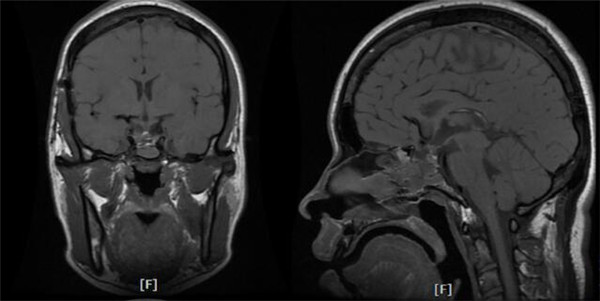

术后复查示正常垂体前后叶均显现,鞍上池形态恢复,未见明显肿瘤残留